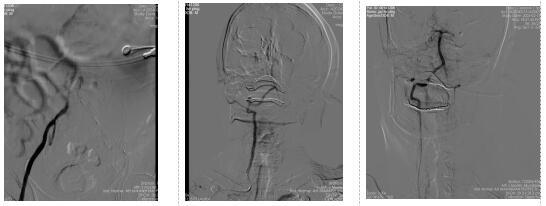

患者病情危重,多模影像學提示基底動脈閉塞,腦干、小腦大片灌注延遲(圖1),立即送往導管室行取栓治療。術中發(fā)現(xiàn)患者雙側(cè)髂動脈閉塞,手術醫(yī)師李志德立即改經(jīng)橈動脈路徑,給予右側(cè)橈動脈置管、取栓,經(jīng)過2個多小時的緊張手術,患者基底動脈血管成功再通(圖2),患者的生命被及時挽救。

圖2 髂動脈閉塞,經(jīng)橈動脈造影確認基底動脈閉塞,取栓治療后基底動脈血流再通